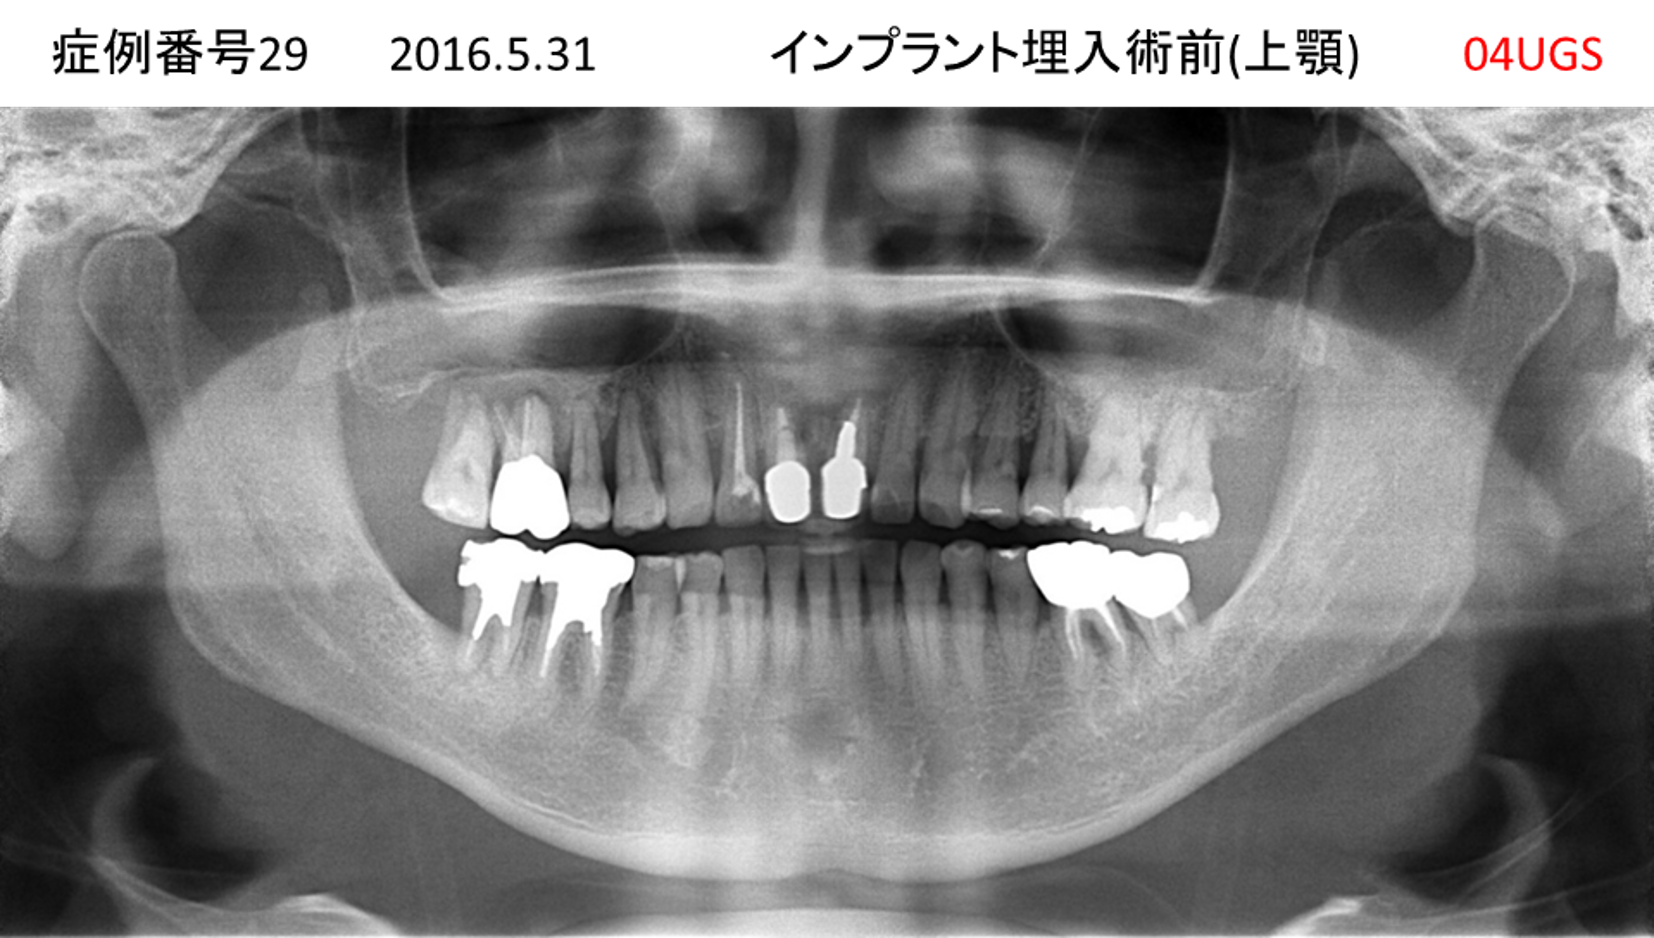

上の前歯が揺れてきてかめない患者様のインプラント症例

| 治療名称 |

インプラント |

| 治療費用 |

440万円+税 |

| 治療期間 |

6か月 |

| 患者さんの症状(主訴) |

上の前歯が揺れてきた。かめない |

| 治療内容 |

サイナスリフト、GBR、インプラント、即時荷重 |

| 治療結果 |

上の前歯の揺れが収まった。奥歯でしっかり噛める。 |

| 治療の注意点(リスク/副作用) |

インプラントが壊れたら再治療が必要 |